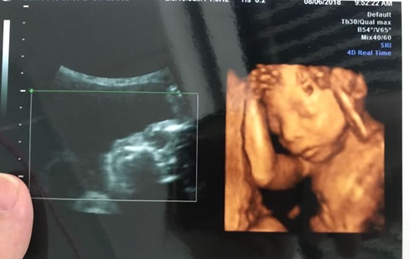

网上流传着四维彩超的报告上如果是有三条线就是女孩,而如果没有三条就是男孩,那么四维女宝宝三条线特征图片长什么样呢,四维男宝也有三条线吗?

其实网上流传着的这种说法并没有依据,原因是网上说的三条线是指女孩生殖器上的线,但是四维彩超上面一般医生是不会显示出完整的生殖器的,还有就是,四维彩超的三条线是无法看出男女性别的,这三条线代表的是脊柱线,还有就是通过三条线来看男女性别的方式误差也是比较大的。

四维彩超其实是实时的三维,是有一个立体成像的过程,因为胎儿是团抱式的,胎儿一部分会被遮挡,所以四维应该会更准确一些,但是不是绝对的。实际在B超进行胎儿性别鉴定时,有可能男孩生殖器被遮挡导致误认为是女孩,因此还是要找专业的医生来看才能下结论。